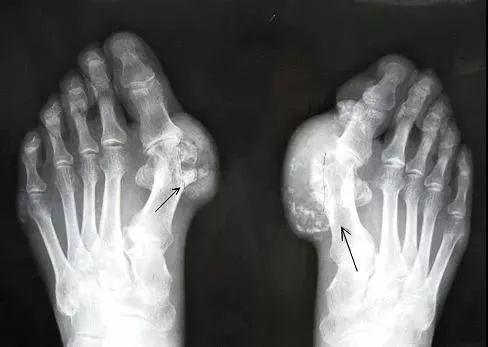

什么是痛风?

所谓痛风

是由尿酸盐沉积导致的

一种晶体相关性关节病

痛风的病因是「高尿酸血症」

就好比水里的盐浓度太高了

慢慢被析出来就形成“尿酸结晶”导致痛风

痛风自然病程一般有4个阶段

1

无症状性高尿酸血症

2

急性痛风性关节炎

3

间歇期

4

痛风石与慢性痛风性关节炎等

痛风性关节炎急性发病期

受累关节会发热、变得暗红、肿胀

感觉有刀割或咬噬样疼痛